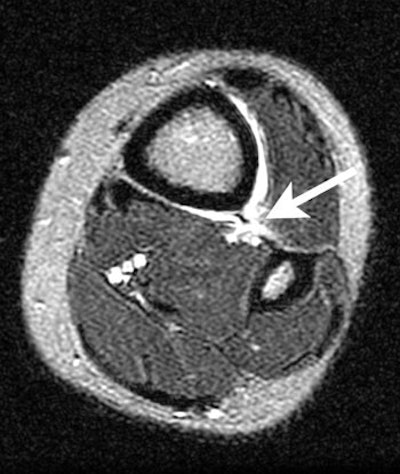

| Coronal FSEIR shows fluid (short arrow) at the anterolateral aspect of the ankle related to the syndesmosis sprain. It also demonstrates sprain of the deltoid ligament (long arrow). |